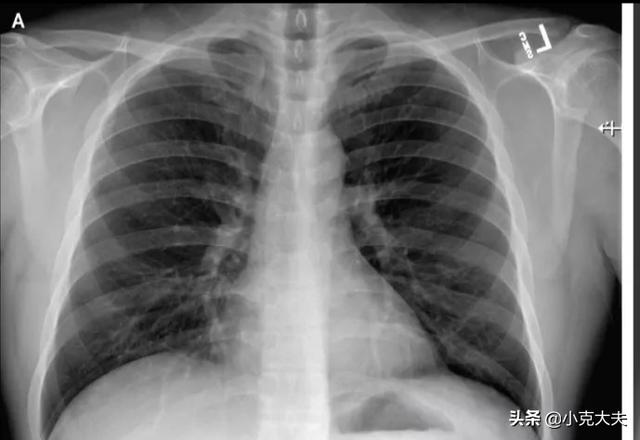

(iii)肺の画像診断では、急性の滲出性病変に有意な改善がみられた;

現在、新型コロナウイルスに対する特効薬はありませんが、積極的な対症療法と抗ウイルス療法により、良好なコントロールと治癒が期待できます。現在、新型コロナウイルス肺炎の接触隔離・退院基準は、①体温が3日以上正常に戻る、②呼吸器症状が著明に改善する、③肺画像検査で急性滲出性病変が著明に改善する、④呼吸器核酸検査が連続2回陰性(2回の検査間隔が24時間以上)、となっている。

今、新しいコロナウイルスの治療基準は非常に明確ではありませんが、感染した患者の要件は、患者の治療後に発熱、乾いた咳などの症状がなく、胸部X線検査が異常なく消失し、連続核酸検査陰性も治癒としてカウントされますが、これらのキャリアの検疫期間が時間内に異常がないかどうかをチェックするために終了している唯一の最初の除外することができると言うことができます。

無症候性感染者とは、ウイルスに感染していても発症せず、発熱、倦怠感、咳などの症状もないが、核酸検査が陽性である患者のことである。自己免疫力が高く、自己免疫系がウイルスの増殖を抑制できる場合もあるが、免疫力が低下すると発症する可能性もある。治癒の基準は、核酸検査が少なくとも2回陰性であること、肺のCTで異常がないこと、感染病巣の著しい吸収がないことである。治癒後、患者は少なくとも14日間隔離される必要があり、その間、特に発熱や咳がある場合は再度チェックする必要がある。現在、成都で治癒した患者が退院10日後に核酸を再検査したところ陽性であった例がある。従って注意が必要である。

実際、国家衛生委員会が発行した最新の「新型コロナウイルス肺炎診断治療プログラム(試行第6版)」によると、今回の新型コロナウイルス肺炎の感染(確定)患者の隔離解除・退院基準は、体温の平熱復帰が3日以上に達すること、呼吸器症状が著明に改善し、肺の画像診断(CT)で急性滲出性病変の著明な改善が認められること、などが詳細に規定されている。ウイルス学的に、呼吸器検体の核酸検査が連続して2回陰性で、サンプリング時期が1日以上離れていること。以上の条件をすべて満たせば、感染者は隔離を解かれ、経過観察のために退院することができる。